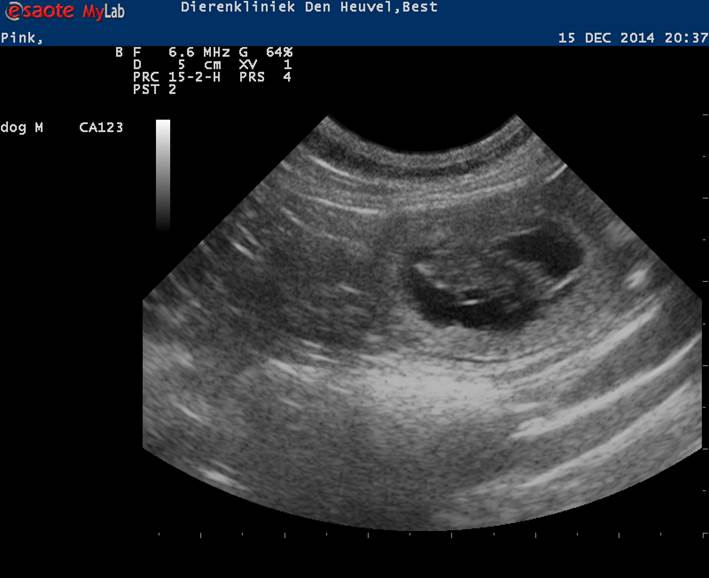

En toen was het tijd voor de echo en ja hoor, ze is hartstikke drachtig!!

Rond 20 januari worden de puppen verwacht.

Hieronder een foto en een filmpje van de echo en de eerste buikfoto's:

Pink 4 weken drachtig